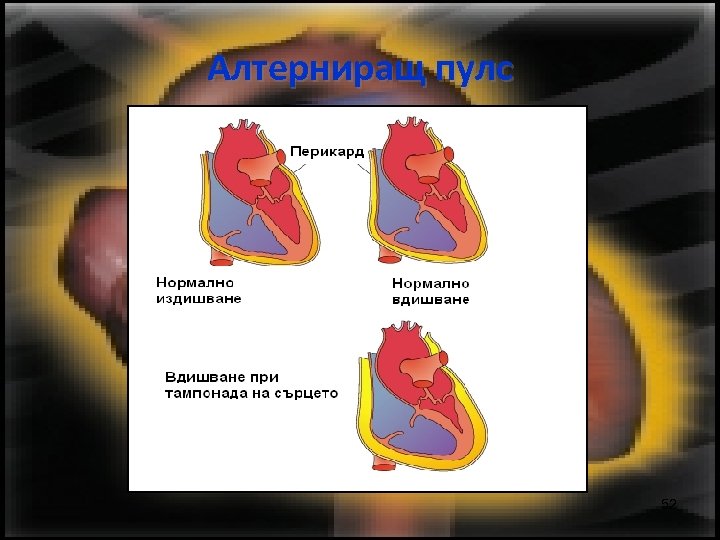

Клинична картина • Триада на Beck: – Глухи тонове на сърцето – Проминиращи шийни вени – Алтерниращ пулс – при дълбоко вдишване изчезва периферния пулс на болния, поради повишаване на налягането в торакалната клетка, и невъзможността сърцето ефективно да се напълни (симптом на Kussmaul). 50

Алтерниращ пулс 52